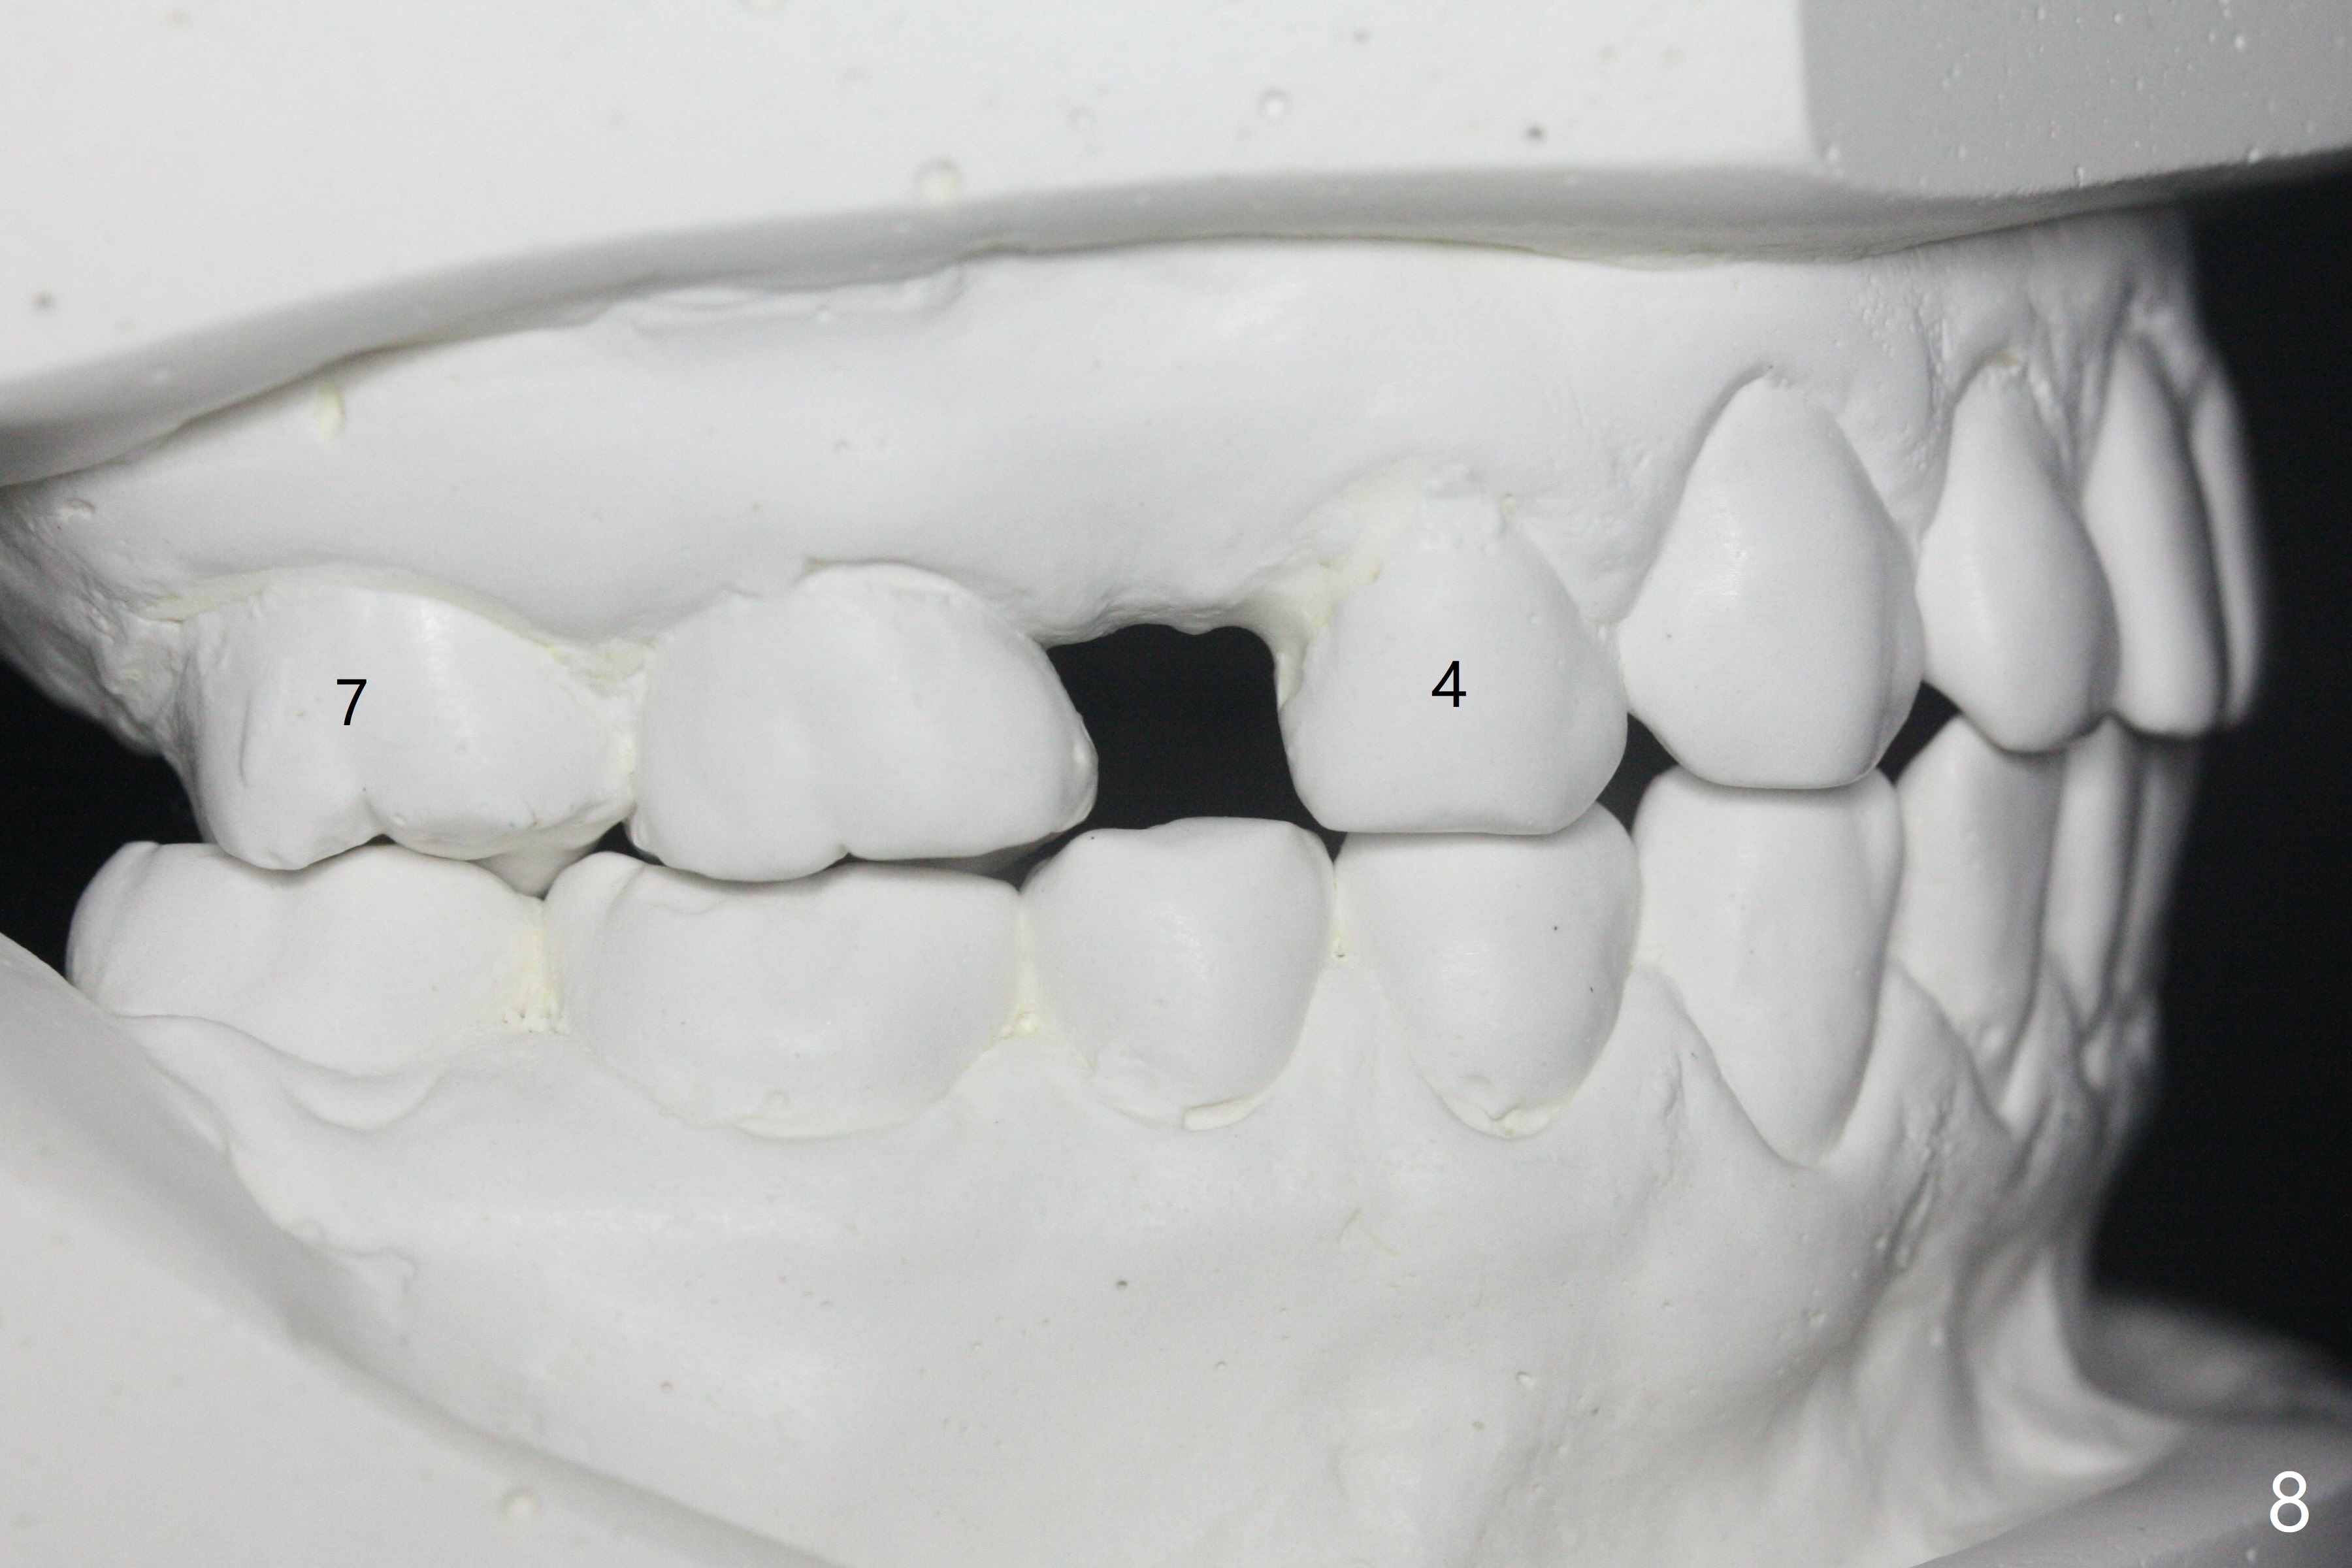

A 40-year-old man requests orthodontics after #17 and 32 extraction. UL5 is missing (Fig.1), while the upper midline deviates to the left (Fig.2 arrow) with crowding between UL2 and 3 (Fig.3). The main goal is to retract UL5 distal and move the upper midline to the right to alleviate UL anterior crowding. Implant will be not needed. To monitor potential root resorption associated with tooth movement, preop PAs are taken (Fig.4-7). The space for an implant at UR5 is narrow. UR4 needs to be distalized using UR7 or a miniimplant distal to UR7 as an anchor (Fig.8). UR4 and 3 will be repositioned to establish Class I occlusion (Fig.9). The space gained by UR4 distalization may be enough to correct the upper midline deviation and UL3 malposition (Fig.10). Brackets will be placed in the lower arch in spite of the normal alignment (Fig.11). UL2 and 3 brackets are unable to be engaged to 14 niti wire (Fig.12). Next visit try to engage UL2 bracket. If not, save the old wire for possible future reuse. Closed spring is placed with 18 ss wire <3 months post banding (coronavirus). Three weeks post closed spring between UR4-7, UR3,4 are being distalized (Fig.13). Distalization of UR4 is not much in 5.5 months (Fig.14,15). It seems necessary to use a miniimplant distal to UR7 as an anchor (Fig.16 white circle), place a long hook mesial to UL4 (more or less root movement instead of tilt) and place the same closed spring between the anchor and hook. In spite of the fact that UR4 seems to have been completely distalized and that UR2 is being distalized 8 months post banding (Fig.18), a 8 mm long mini-implant is placed in the maxillary tuberosity with minimal local anesthetic (Fig.17,19). A longer closed spring (18 mm) is placed between the implant and UR3 hook (Fig.20). Next appointment a lingual button will be placed at UR4 for rotation, while a post hook mesial to UR3 for torque. UR3 distalizes with the help of UR mini-implant, which is unfortunately loose. Next visit place lingual button at UR4 (Fig.21 arrow) to distalize the lingual cusp. Crimpable power hook is placed mesial to UR2 for distalization (for root torque, Fig.22). If it works, remove the wire and reposition the hook for UR1 next visit. UR2 is distalized in one appointment (~ 1 month, Fig.23, as compared to Fig.22). With lingual button at UR4, rotation seems to have been corrected shortly (Fig.24 arrow).